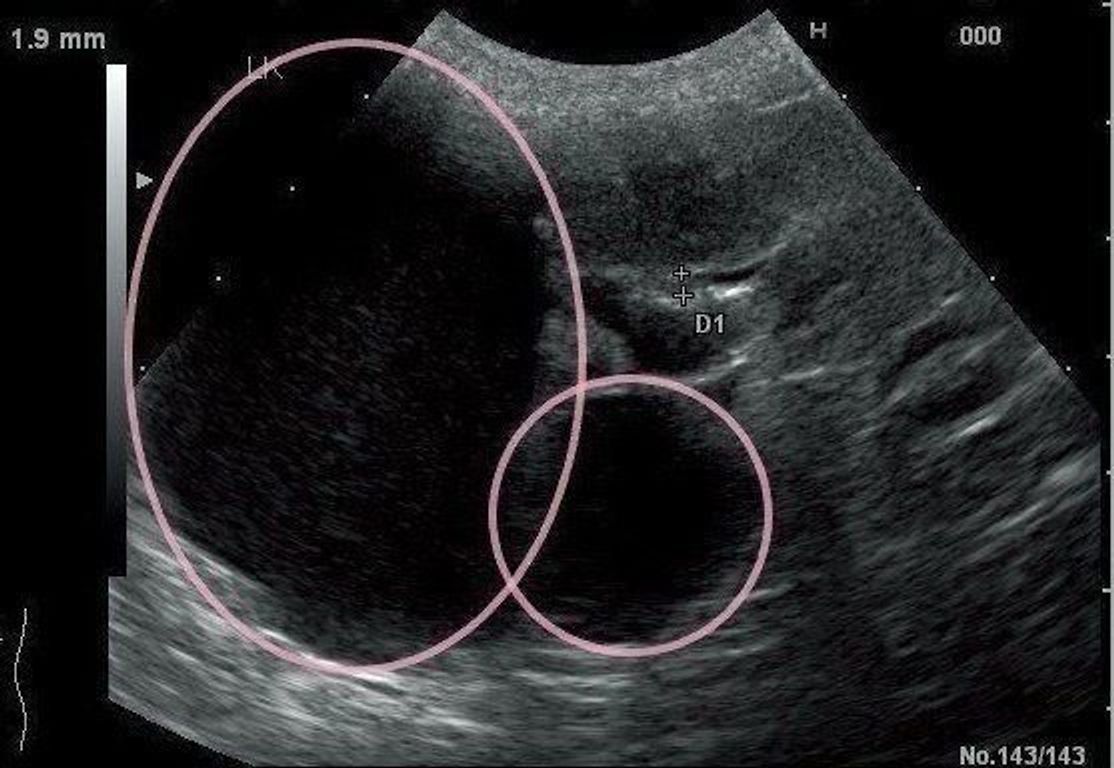

腎臓疾患の超音波像あれこれ 腹部超音波検査vol 8 腎臓編パート2 心臓弁膜症 手術 みどり病院 神戸市西区